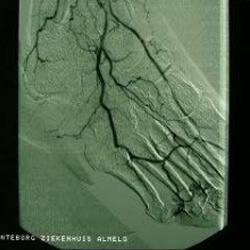

Ischemie is naast de neuropathie en infectie een belangrijke complicatie bij suikerziekte en leidt tot de aantasting van de bloedvaten. Hierdoor kunnen doorbloedingsstoornissen ontstaan in de onderbenen en de voeten en spreken we van een ischemische voet.

De doorbloedingsstoornissen worden veelal laat opgemerkt doordat de pijn bij het lopen (een gebruikelijke uiting van doorbloedingsstoornissen in het been) door de neuropathie ontbreekt. Ook speelt de gedachte een rol dat suikerziekte meestal een ziekte is van de ouderen die minder mobiel zijn.